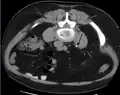

Otherwise a noncontrast helical CT scan with 5 millimeters (0.2 in) sections is the diagnostic method to use to detect kidney stones and confirm the diagnosis of kidney stone disease.[14][53][56][61][7] Near all stones are detectable on CT scans with the exception of those composed of certain drug residues in the urine,[55] such as from indinavir.

Bilateral kidney stones can be seen on this KUB radiograph. There are phleboliths in the pelvis, which can be misinterpreted as bladder stones.

Measurement of a 5.6 mm large kidney stone in soft tissue versus skeletal CT window.